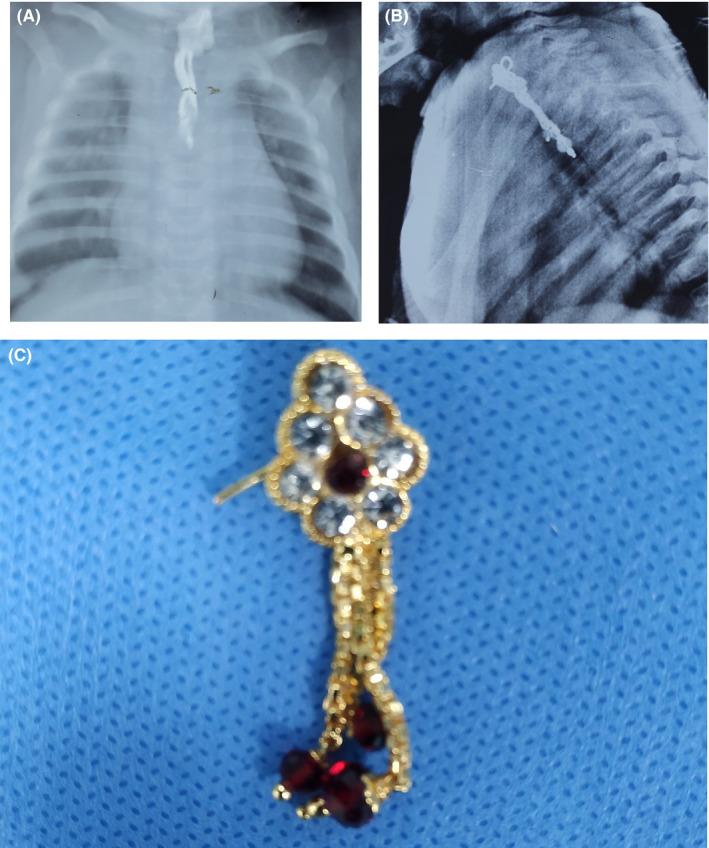

Foreign body esophagus in a young infant.

Unattended children, mostly from low-socioeconomic contexts, who present with sudden onset obstructive respiratory and/or gastrointestinal symptoms, should be at high suspicion for foreign body ingestion. Prompt diagnosis helps avoid mismanagement and can potentially avoid dire outcomes.